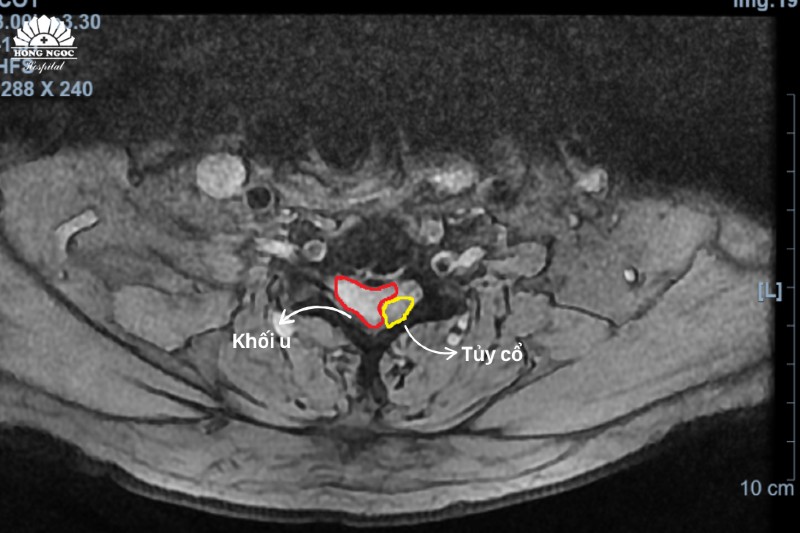

Khối u chiếm ½ tủy cổ từ mặt cắt ngang phim chụp cột sống cổ.

Trực tiếp thăm khám cho bệnh nhân, PGS.TS.BS Hà Kim Trung (Chuyên gia hơn 30 năm phẫu thuật thần kinh, cột sống - BVĐK Hồng Ngọc) chia sẻ, u màng tủy cổ là bệnh lý hiếm gặp với các biểu hiện không rõ ràng, dễ nhầm lẫn với các triệu chứng của thoái hóa, thoát vị đĩa đệm cột sống. Kết quả chụp MRI cho thấy khối u đã chèn ép 1/2 ống tủy, khiến bệnh nhân có biểu hiện tê bì - yếu tứ chi.